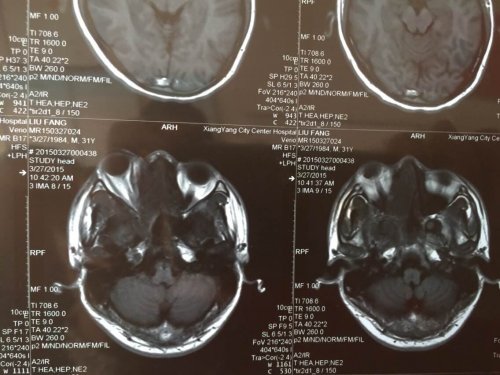

03—27 影像图:

04—15 影像图

03—27 影像图:

04—15 影像图